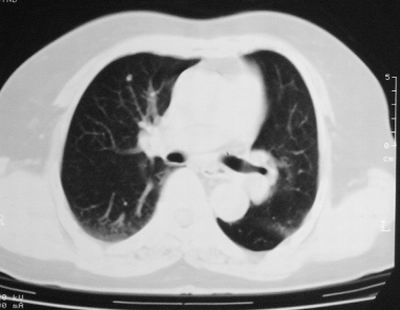

患者,女,64岁,4年前左腮腺"多形性"腺瘤手术治疗史.现复查胸部ct见左下肺块状影,该影与原左腮腺手术是否有联系?

本次复查胸部ct

左下肺软组织块影,有分叶、毛刺、空泡及胸膜牵拉征,左下肺周围性肺癌。

左肺下叶周围型肺癌,支持!(软组织肿块+分叶+毛刺+空泡+胸膜凹陷征)

左下肺软组织密度影,可见分叶,边缘可见毛刺征,胸膜增厚,强烈要求左下肺周围型肺癌

左下肺后基底段实性肿块,周围有毛刺,病变周围有肺气肿,与降主动脉间有条带状影相连,病灶4年前查体发现,纵隔内未见肿大淋巴结。考虑.肺隔离症,建议增强扫描与周围型肺癌鉴别。